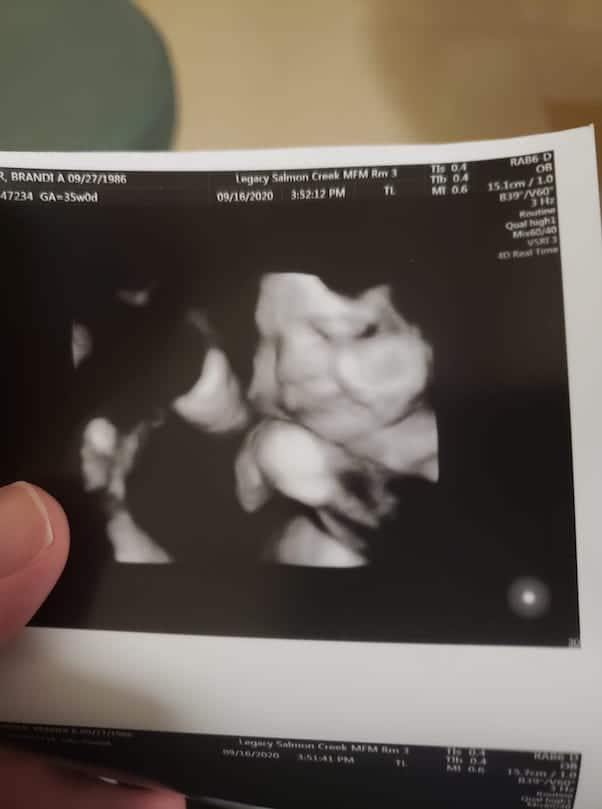

Brandi Dreier shared a shot of her ultrasound in September just under a month before her due date. Guess what? It’s going to be a girl and here is what Brandi wrote while sharing the picture. She said that her second daughter wanted to show off her smile. So here she is all smiling while she is just a few weeks away from being with everyone. She further wrote that she is truly blessed for having her children. On another note, Brandi is not going to have a baby shower due to the pandemic. However, the mom-to-be added that she has a baby registry via Amazon so people can definitely spoil her girl!